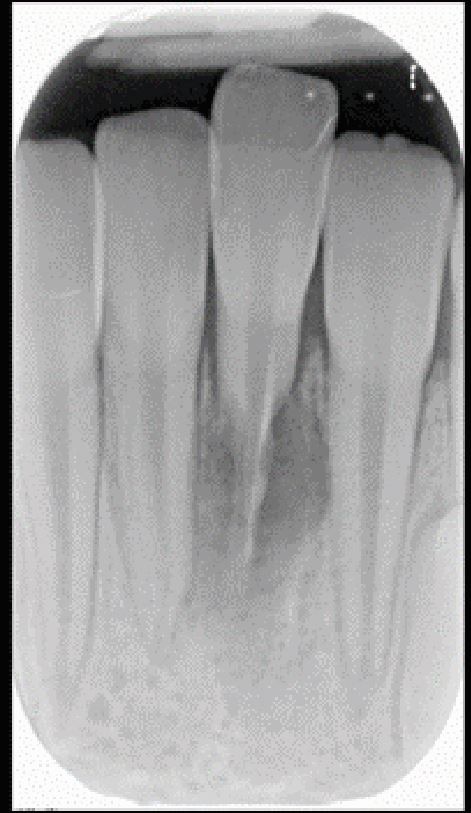

Fig. 1

From: Getting it right at every stage: Top tips for traumatic dental injury review: Part 1

Tooth 31 was replanted following avulsion. The patient re-attended some four months later, having missed intervening appointments. Replacement resorption is seen and the outlook for 31 hopeless